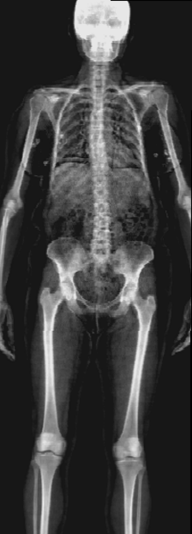

In this work, we present X-Diffusion, a cross-sectional diffusion model tailored for Magnetic Resonance Imaging (MRI) data. X-Diffusion is capable of generating the entire MRI volume from just a single MRI slice or optionally from few multiple slices, setting new benchmarks in the precision of synthesized MRIs from extremely sparse observations. The uniqueness lies in the novel view-conditional training and inference of X-Diffusion on MRI volumes, allowing for generalized MRI learning. Our evaluations span both brain tumour MRIs from the BRATS dataset and full-body MRIs from the UK Biobank dataset. Utilizing the paired pre-registered Dual-energy X-ray Absorptiometry (DXA) and MRI modalities in the UK Biobank dataset, X-Diffusion is able to generate detailed 3D MRI volume from a single full-body DXA. Remarkably, the resultant MRIs not only stand out in precision on unseen examples (surpassing state-of-the-art results by large margins) but also flawlessly retain essential features of the original MRI, including tumour profiles, spine curvature, brain volume, and beyond. Furthermore, the trained X-Diffusion model on the MRI datasets attains a generalization capacity out-of-domain (e.g. generating knee MRIs even though it is trained on brains). The code is available on the project website https://emmanuelleb985.github.io/XDiffusion/.

Recently, the use of diffusion-based models for image inverse problems has shown great success [63, 18, 35, 51, 40, 52]. This motivated our X-Diffusion to investigate learning volumes instead of images. In this light, our X-Diffusion proposes a novel architecture to allow learning on 3D volumetric data by view-dependent cross-sections. This allows for full MRI generation with unprecedented accuracy from a single MRI slice, multiple slices, or even from DXA image if paired data is available (see Figure 1). To the best of our knowledge, X-Diffusion is the first work to successfully generate detailed MRI volumes from a single DXA scan, bridging the gap between two common data modalities in medical imaging. It is important to note that the generated MRIs are not clinical replacements for true MRIs, but could provide a quick, affordable, and informative “pseudo-MRI" before conducting a full MRI examination.

Contributions: (i) We introduce X-Diffusion, a cross-sectional diffusion model that generates MRI slices conditioned on a single input MRI slice or multiple slices. The proposed X-Diffusion achieves state-of-the-art results on MRI reconstruction and super-resolution compared to recent methods on BRATS, a large public dataset of annotated MRIs for brain tumours. (ii) We adapt our X-Diffusion to leverage paired and registered full-body MRI and DXA images from UK Biobank dataset to generate full-body 3D MRI from a single DXA for the first time in the literature. (iii) We validate the generated MRIs on a wide range of tasks that ensure the generated MRIs retain important features of the original MRIs, including tumor profiles, spine curvature, brain volume, and more, without using this meta-information in the generation process. (iv) We showcase the generalization of trained X-Diffusion on different datasets (knee MRIs) illustrating the potential of X-Diffusion to be the first 3D volumetric foundation model in medical imaging.